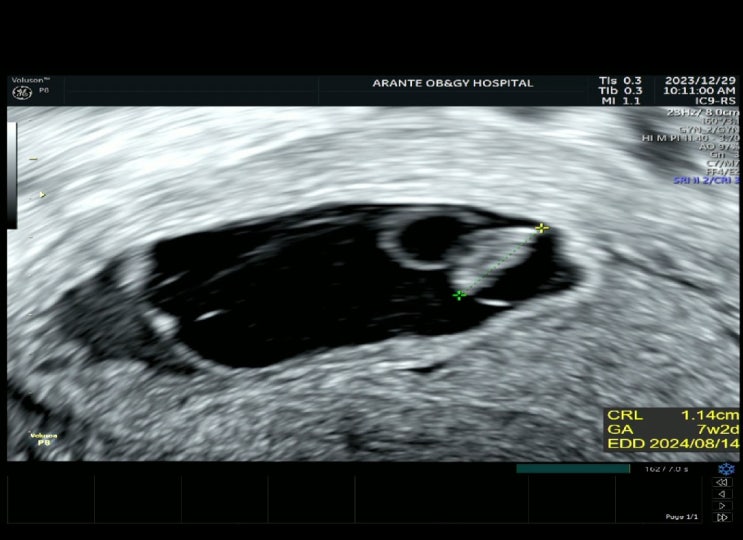

계류유산 후 임신이 되었다. 임밍아웃은 최대한 늦게, 25주까지의 기록

이 포스팅을 언제 써야 하나 고민이 많았는데, 이제는 정말 안정기에 들어온 것 같다는 생각이 들어 기록을...

계류유산 증상 너를 품었던 9주 동안의 기록.

큰 굴곡 없이, 보통의 범주 속에서 살아온 나였기에 아기도 그냥 생기는 줄 알았고 생기면 그냥 낳을 수 있...